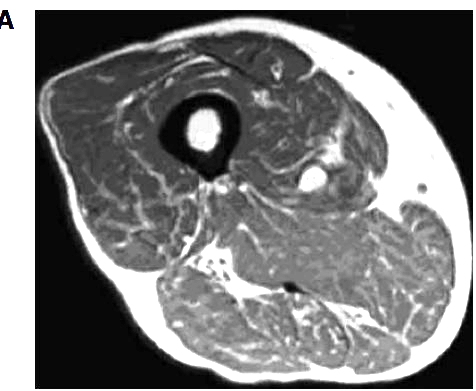

Figure 2

Magnetic resonance imaging of two different grades of fatty degeneration and atrophy involving thigh muscle in patients with vitamin D deficiency.

A Grade 1 (less than 30% of the volume of muscles involved);

B: Grade 2 (30%-60% of the volume of muscles compromised).

For illustration, Figure 2 shows MRI of two different grade of fatty atrophy involving thigh muscle in patients with vitamin D deficiency. The hypothesis that arose was that atrophy of skeletal muscle fibers and their replacement by fat tissue are the anatomic basis for the impairment in muscular performance described in older vitamin D-deficient people[4]. It may supposed that fatty substitution related to vitamin D deficiency may be the result of the lack of the known trophic effects of vitamin D on skeletal muscle cells[4]. If the thigh muscles are affected, the lack of enough muscular bulk may hamper balance and gait. Clinical scores were concordant with this observation. Concerning technical MRI protocols we suppose that a standard, patient-friendly protocol, including T1 and T2 weighted sequences may be sufficient for the follow-up of elderly people with potential vitamin D deficiency. In another study of 366 older patients receiving MRI of one shoulder for the investigation of potential rotator cuff injury, a correlation between higher fatty infiltration of rotator cuff muscles and lower serum levels of 25D was reported[22] . After multivariate linear regression analysis, this association remained statistically significant in two muscle groups (i.e., supraspinatus and infraspinatus muscles) but only among those whose MRI also demonstrated a full-thickness rotator cuff tear (228 patients).